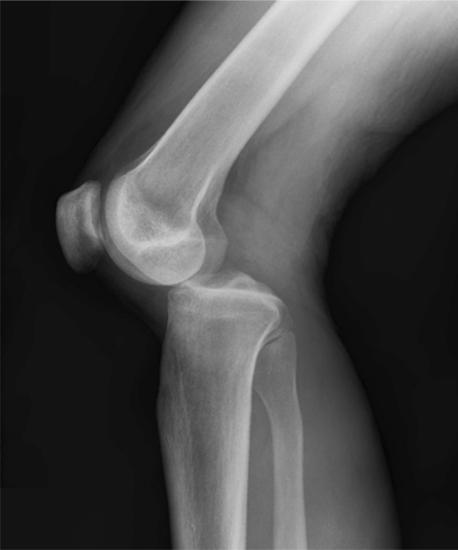

Clinical image for Multi-Ligament Knee Injury

What is the definition of knee dislocation? Describe the classification and associated injury patterns.